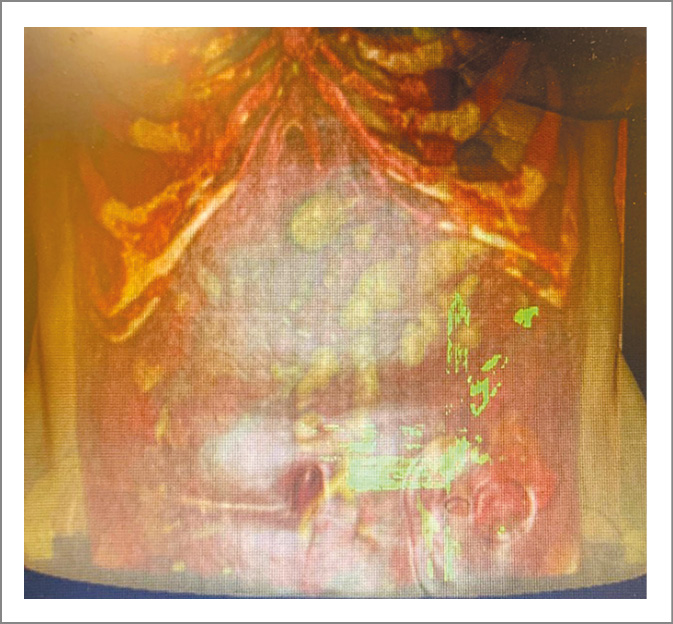

Рис. 4. Участки кишки, максимально припаянные к передней брюшной стенке.

Методику выполнения хирургического доступа и его локализацию, учитывая распространенность спаечного процесса, рассчитали с помощью 3D-моделирования сегментированного изображения (рис. 2–4). В автоматическом режиме выделены пиксели плотностью от -226 HU до 3071 HU, что соответствовало рентгенплотности кожи и подкожной клетчатки. Проведенное исследование позволило выделить зоны адгезии толстой и тонкой кишки к брюшной стенке, представляющие повышенную опасность для выполнения доступа.

Следующим этапом с использованием метода сегментации изображения и 3D-моделирования в ручном режиме выделены наиболее значимые энтеропариетальные и межкишечные спайки – спроецированы на переднюю брюшную стенку (рис. 5).

Рис. 5. 3D-моделирование изображения брюшной полости пациента.

Зеленым цветом отмечены участки кишки, плотно спаянной с передней брюшной стенкой.

Таким образом, исключив опасные места для выполнения лапаротомии, определили области для безопасного введения лапароскопических троакаров. Точку для введения первого троакара обозначили на границе средней и верхней трети прямой мышцы живота слева.